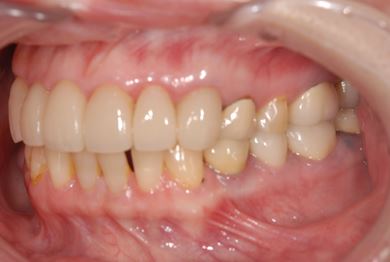

| 性別/年齢 | 女性 / 51歳 | ||||||||||||||||||||||||||||||||

| 主訴 | 前の歯の治療後の変色が気になる。詰め物がとれた箇所あり。痛みあり。 | ||||||||||||||||||||||||||||||||

| 治療方針 | セラミック治療にて、審美的回復を行う。 | ||||||||||||||||||||||||||||||||

| 治療内容 | オールセラミッククラウン7本(オールセラミック用土台1本)、ハイブリッドセラミッククラウン10本(ハイブリッドセラミック用土台9本)、ハイブリッドセラミックインレー1本 | ||||||||||||||||||||||||||||||||

| 総治療費 | 961,800円 | ||||||||||||||||||||||||||||||||

| 治療期間 | 10ヶ月 |